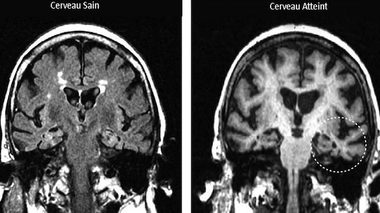

Maladie de Parkinson : le principal suspect est coupable

Les chercheurs accusent une protéine, l'alpha-synucléine, d'induire la maladie de Parkinson